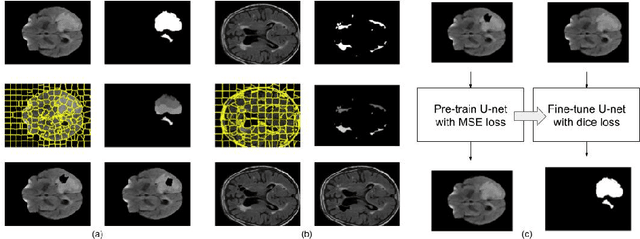

Abstract:The paradigm of self-supervision focuses on representation learning from raw data without the need of labor-consuming annotations, which is the main bottleneck of current data-driven methods. Self-supervision tasks are often used to pre-train a neural network with a large amount of unlabeled data and extract generic features of the dataset. The learned model is likely to contain useful information which can be transferred to the downstream main task and improve performance compared to random parameter initialization. In this paper, we propose a new self-supervision task called source identification (SI), which is inspired by the classic blind source separation problem. Synthetic images are generated by fusing multiple source images and the network's task is to reconstruct the original images, given the fused images. A proper understanding of the image content is required to successfully solve the task. We validate our method on two medical image segmentation tasks: brain tumor segmentation and white matter hyperintensities segmentation. The results show that the proposed SI task outperforms traditional self-supervision tasks for dense predictions including inpainting, pixel shuffling, intensity shift, and super-resolution. Among variations of the SI task fusing images of different types, fusing images from different patients performs best.

Abstract:Self-supervised learning has proven to be invaluable in making best use of all of the available data in biomedical image segmentation. One particularly simple and effective mechanism to achieve self-supervision is inpainting, the task of predicting arbitrary missing areas based on the rest of an image. In this work, we focus on image inpainting as the self-supervised proxy task, and propose two novel structural changes to further enhance the performance of a deep neural network. We guide the process of generating images to inpaint by using supervoxel-based masking instead of random masking, and also by focusing on the area to be segmented in the primary task, which we term as the region-of-interest. We postulate that these additions force the network to learn semantics that are more attuned to the primary task, and test our hypotheses on two applications: brain tumour and white matter hyperintensities segmentation. We empirically show that our proposed approach consistently outperforms both supervised CNNs, without any self-supervision, and conventional inpainting-based self-supervision methods on both large and small training set sizes.